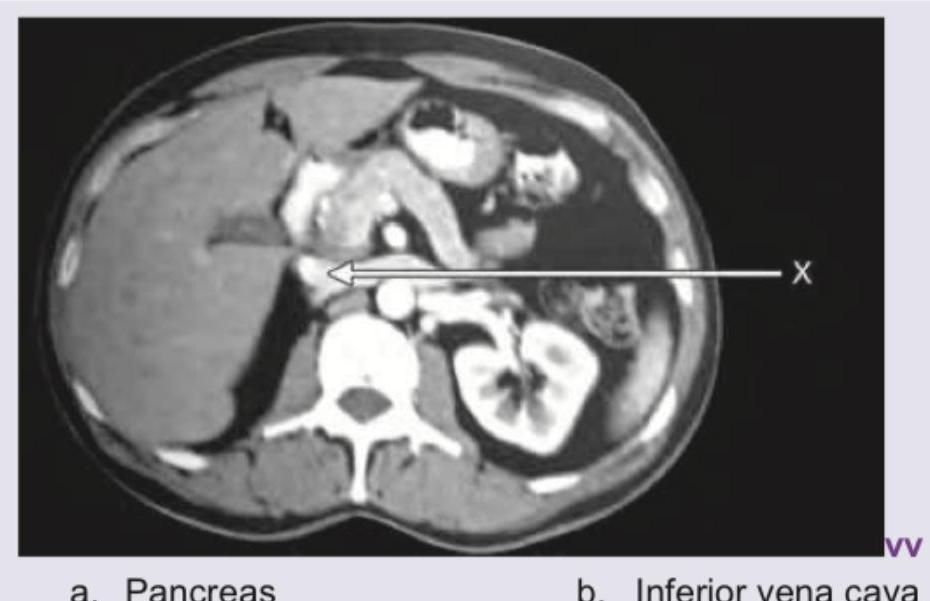

Name the structure marked as $X$ in the CT abdomen shown below: (Recent NEET Pattern 2016-17)

Explanation: ***Inferior vena cava*** - The structure marked as X is located to the **right of the aorta** and is typically seen as a large, relatively **thin-walled vessel**. - Its position anterior and to the right of the vertebral body, draining into the heart, is consistent with the **inferior vena cava (IVC)**. *Pancreas* - The pancreas is typically located more anteriorly and superiorly in this cross-section, usually nestled between the duodenum and spleen. - It would appear as a **glandular organ** with a different texture and position on a CT scan. *Aorta* - The aorta is typically the **larger, thick-walled, pulsatile vessel** located to the **left of the vertebral body** and to the left of the structure marked X. - It usually appears circular in cross-section and is often seen with higher attenuation due to arterial contrast. *Left renal vein* - The left renal vein typically arises from the left kidney and crosses the midline to drain into the IVC, passing **anterior to the aorta**. - The structure marked X is the IVC itself, which receives the left renal vein, rather than the left renal vein.